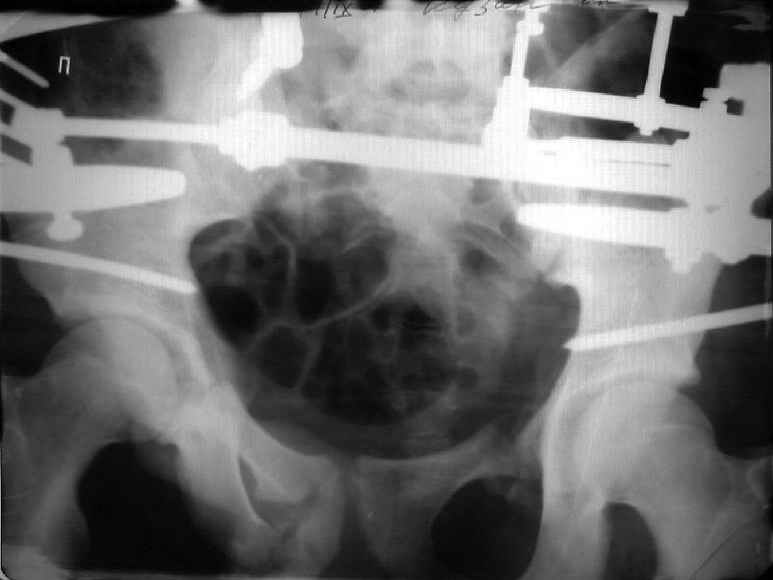

Для информации к размышлению о возможности исправления имеющейся деформации предлагаю похожий случай.